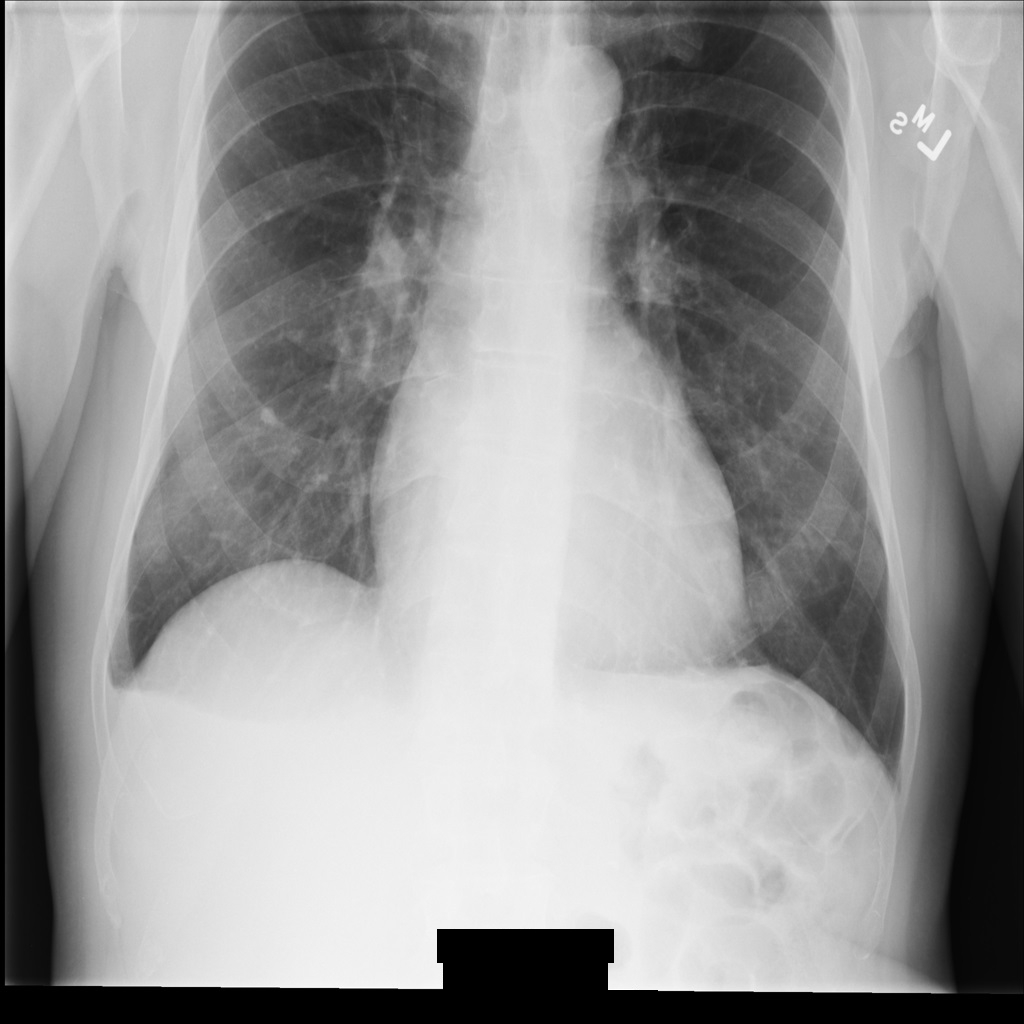

Contoh gambar

Beberapa contoh di halaman ini berisi output gambar yang tidak diidentifikasi. Setiap sampel menggunakan gambar asli berikut sebagai inputnya. Anda dapat membandingkan gambar output dari setiap operasi penghapusan identitas dengan gambar asli ini untuk melihat efek operasi:

Setelah gambar di-de-identifikasi menggunakan REDACT_ALL_TEXT, gambar

akan terlihat seperti ini. Perhatikan bahwa semua teks permanen di bagian bawah gambar telah disamarkan.

Setelah gambar di-de-identifikasi menggunakan REDACT_SENSITIVE_TEXT_CLEAN_DESCRIPTORS, gambar

akan terlihat seperti ini. Perhatikan bahwa tidak semua teks permanen di bagian bawah gambar telah disamarkan. Teks Female masih ditampilkan, karena

PatientSex (0010,0040) bukan salah satu infoType DICOM default.